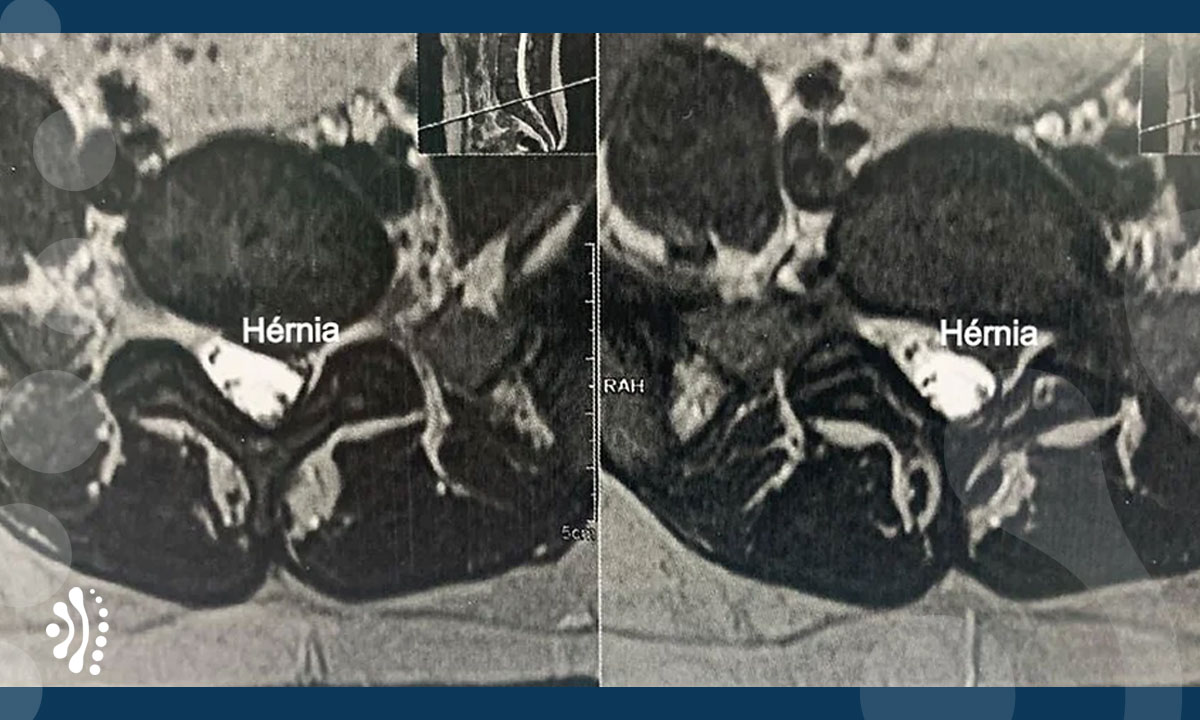

Abaixo, imagem de paciente com hérnia protrusa que apresentava alteração na eletroneuromiografia ou estudo dos nervos na perna e dores incapacitantes há 2 anos, sem resposta ao tratamento clínico. Esse paciente, por ser jovem, foi tratado com prótese discal lombar que objetiva preservar os movimentos em pacientes jovens e evitar degeneração do nível de cima de onde foi realizada a cirurgia. Isto ocorre em 10 a 20% dos pacientes submetidos a artrodese ou fixação da coluna.